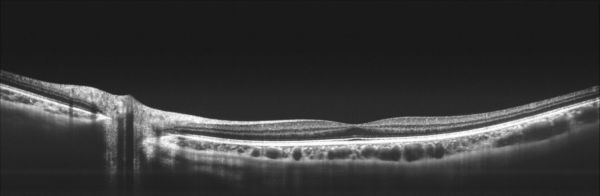

16mm视盘-黄斑区断层成像(团队供图)